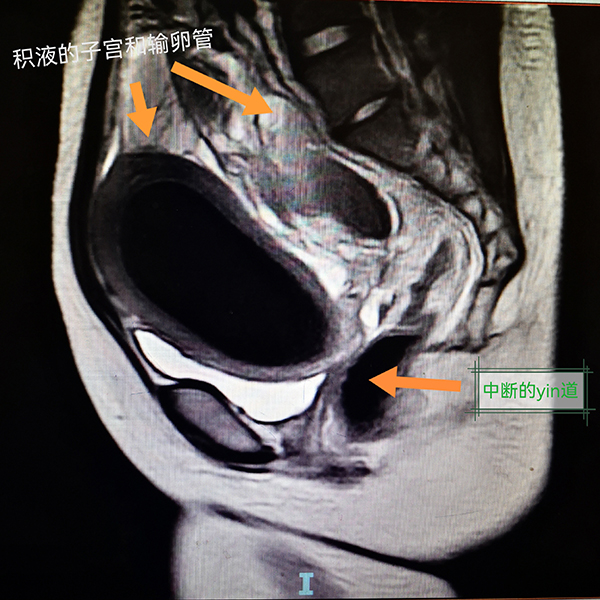

入院后,小楊進(jìn)一步完善了腹部MRI等相關(guān)檢查,結(jié)果顯示她的病情比醫(yī)生預(yù)知的情況更復(fù)雜。小楊的陰道只有約1cm長(zhǎng),宮頸陰道全程實(shí)性梗阻;盆腔增強(qiáng)磁共振考慮宮頸、陰道發(fā)育異常,宮頸閉鎖可能,伴宮腔積液/積血;左下腹-盆腔內(nèi)良性囊性腫塊,考慮左側(cè)附件來(lái)源病變,出血性囊腫可能;雙側(cè)輸卵管擴(kuò)張、積液/積血;考慮盆腔包裹性積液,伴盆腔腹膜滲出改變。經(jīng)過(guò)多學(xué)科聯(lián)合診療,醫(yī)生決定為小楊實(shí)施經(jīng)陰道陰道成型術(shù)+宮頸探查+成型術(shù)+腹腔鏡探查+左側(cè)卵巢囊腫剔除+雙側(cè)輸卵管傘端造口+腸粘連松解術(shù)。